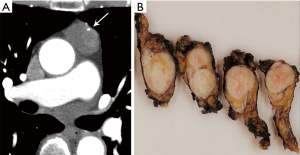

CT plays a major role in the diagnosis and characterization of thymoma. CT imaging has been found to have 88.5% sensitivity and 77% specificity for thymoma, based on a case series of 104 patients with myasthenia gravis (22). On imaging, thymoma may not conform to the shape of normal thymic tissue. Thymoma usually presents as a smoothly-circumscribed, encapsulated soft-tissue density lesion (3) (Figure 1), often homogeneous in enhancement. Calcification may be seen, and is more common in invasive rather than noninvasive (encapsulated) thymomas (23). Areas of necrosis, cystic change, or hemorrhage are less common (3).

The hallmark of the histological diagnosis of thymoma is the presence of two cell populations, one comprised of epithelial cells and another of immature lymphocytes (Figure 4). However, this classic feature may not be present in many cases due to sampling and histological variation. Immunohistochemical (IHC) stains are very helpful as the thymocyte epithelial cells are positive for keratin, whereas immature lymphocytes are positive for TdT. There must be close co-localization of the two cell populations, as the markers individually are not specific for the diagnosis of thymoma and can be seen in other entities. As an example, TdT positive lymphocytes are present in acute lymphoblastic lymphoma, a common lymphoproliferative disorder of the mediastinum in children and younger adults. The immature (TdT positive) lymphocytes are also seen in metastatic thymoma, a useful diagnostic feature for the diagnosis of thymoma outside of the mediastinum.